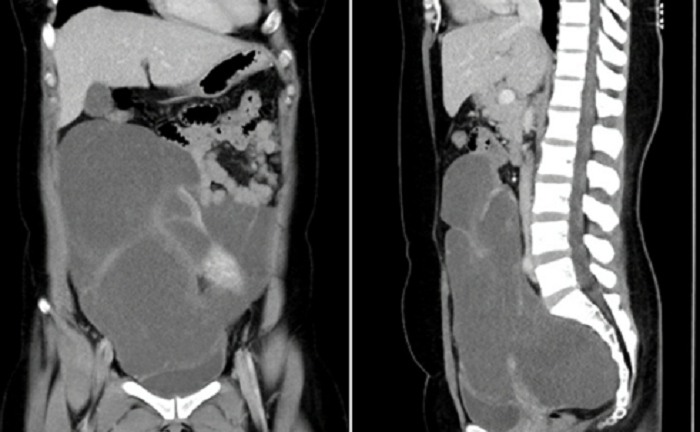

Khối u trong bụng chị A. chiếm hết 2/3 ổ bụng, chèn ép ruột, bọng đái lại dính vào ruột non, ruột già, tử cung, buồng trứng, vách chậu... khiến bác sĩ không khỏi đau đầu khi phẫu thuật.